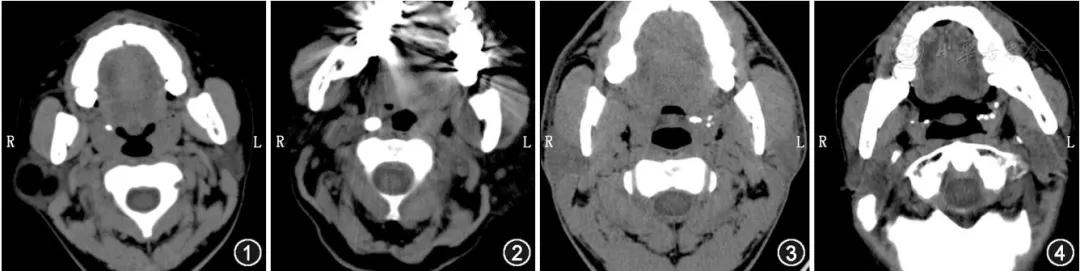

扁桃体结石常单侧发病,结石大小不一,小者如沙粒,大者如鸽卵。 临床表现类似于慢性咽炎的症状,主要是反复咽痛、咽部异物感及伴有口臭。 扁桃体结石的主要成分是磷酸盐,所以CT上呈致密影。

上图分别为CT显示的:右侧扁桃体单发小结石、右侧扁桃体单发较大结石、左侧扁桃体多发结石、双侧扁桃体多发结石

丨参考文献1